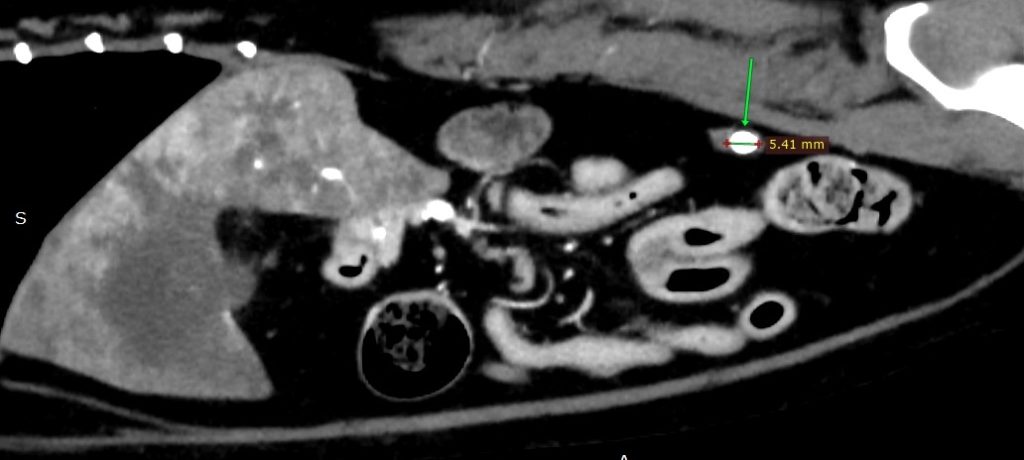

尿管結石あり